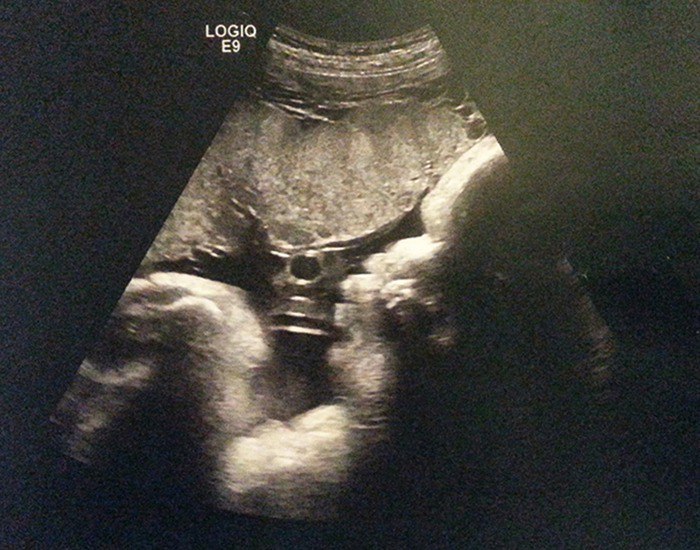

Homiladorlik

37-hafta

Tug‘ilishga 3 hafta bor